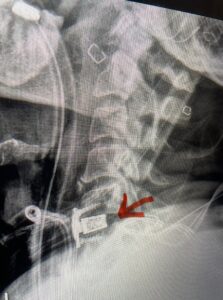

The case illustrates a more subtle finding of cervical myelopathy in a young 52 year-old male who presents with 5 months of left upper extremity weakness and burning. He also had developed over the last two months pain in his right upper extremity. He also had difficulty with fine motor skills. He had a positive Hoffman reflex and mild 4-4+ long tract weakness of his left arm and leg. Cervical MRI revealed an explanation for the patient’s symptoms (Fig. 7) as it revealed a disc osteophyte complex causing some cord flattening, slightly more to the left. We performed a C5-6 anterior cervical discectomy and interbody fusion with cage and plate (Fig. 8) He had a significant improvement in his weakness, numbness, and pain. What is interesting is that this was a relatively young patient without severe cord compression but was significantly affected by a mild amount of cord compression. This may speak to how a younger spinal cord may react much more adversely perhaps secondary to a less compliant spinal cord.

Fig. 7a Sagittal and axial T2-weighted cervical MRI’s demonstrating spinal cord compression slightly to the left secondary to disc/osteophyte complex (red arrow)

Fig. 7b

Fig 8: lateral intraoperative cervical x-ray demonstrating placement of interbody cage and plate at C5 6 (red arrow)